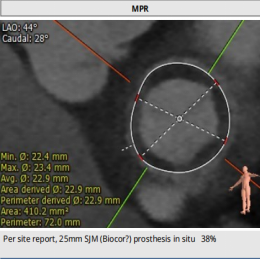

术前经详尽评估患者病情,通过CT重建测量瓣环直径、左室流出道面积。综合评估决定对该病例采用经静脉途径行二尖瓣“瓣中瓣”手术。既往植入25#St jude生物二尖瓣,测量支架内径22.9mm,选用23#SAPIEN 3球扩式瓣中瓣。虽手术过程异常艰难,但最终瓣中瓣植入位置理想,左室造影及经食道超声观察无明显瓣中及瓣周反流。瓣中瓣植入后观察左房峰值压明显下降,二尖瓣平均跨瓣压差降至3mmHg。